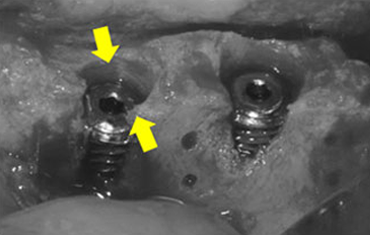

타 치과의 뼈 이식 후 골조직

램브란트치과 상인점 뼈이식 후 골조직

임플란트 식립과 동시에 뼈이식을 하는 경우

폭이 많이 부족하여 뼈이식을 먼저 한 후, 임플란트 식립을 하는 경우